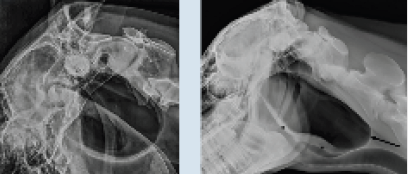

Radiographie montrant la poche remplie d’air